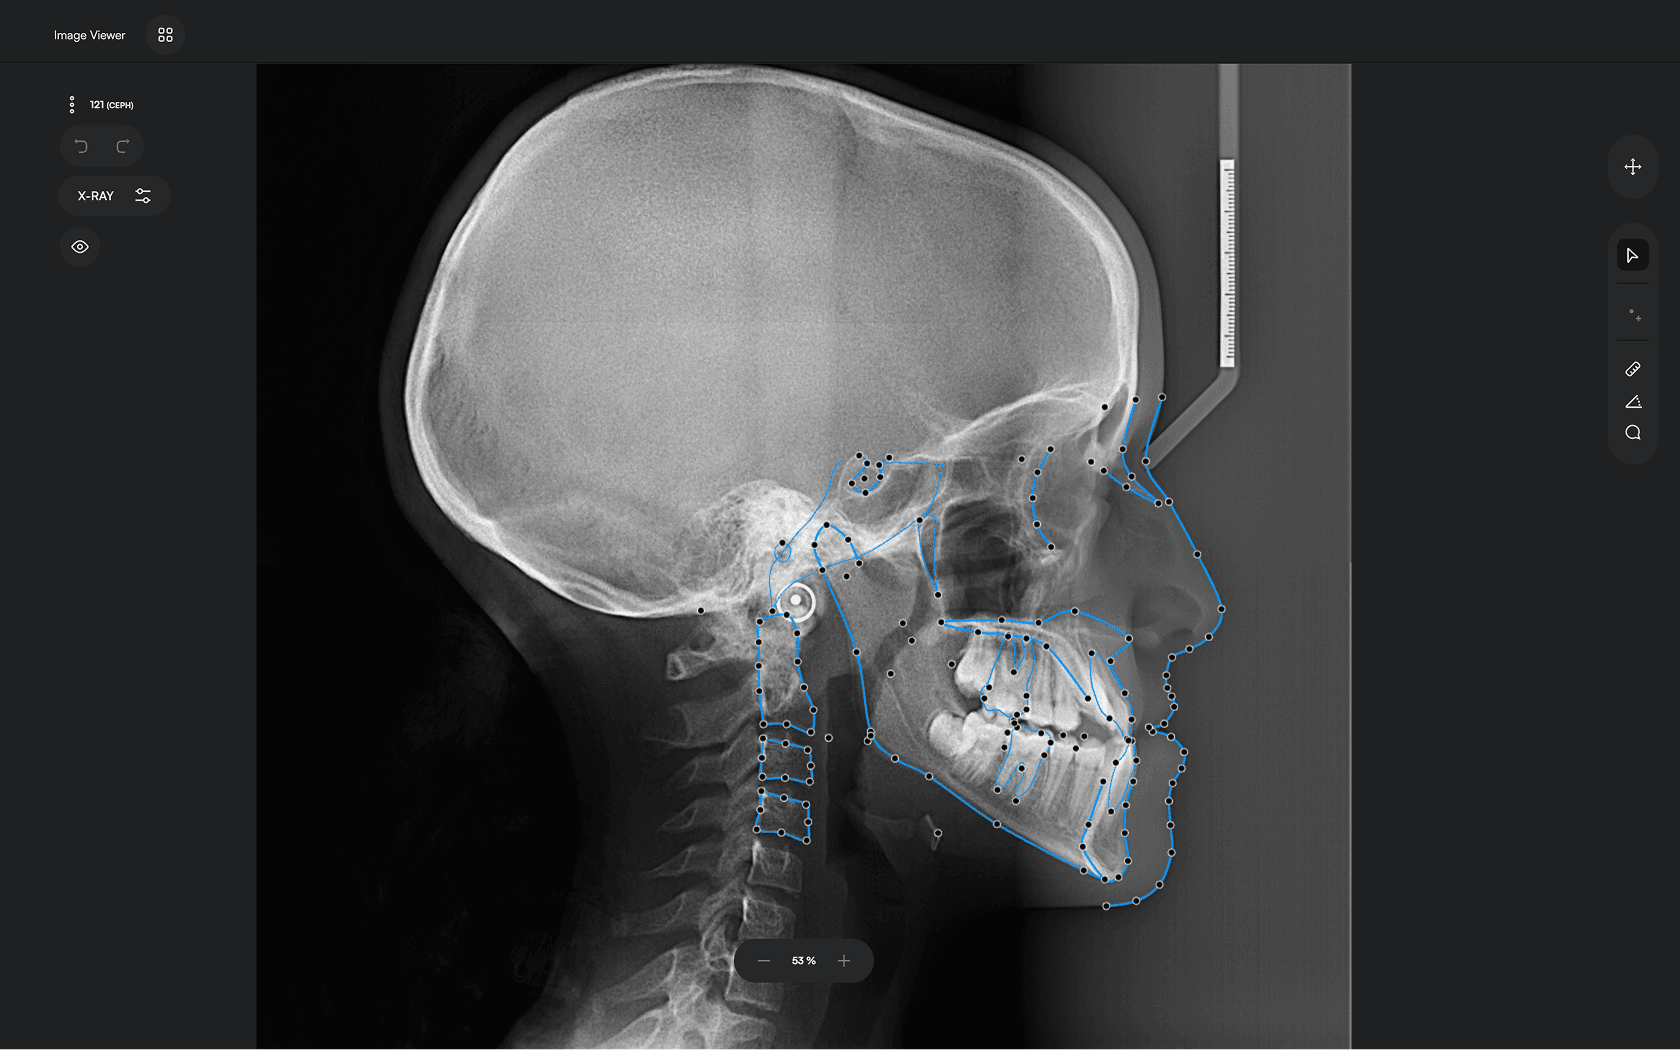

150+ landmarks traced in seconds

Identify 150+ orthodontic landmarks in under 10 seconds — a task that

traditionally may take more than 30 minutes.

Experience a comprehensive assessment of skeletal, dental, and soft tissue discrepancies.